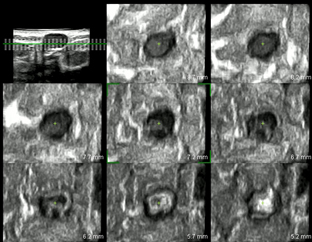

乳線良性腫瘤の水平面の超音波像

腫瘤と周囲組織の境界は明瞭に表示されている。

乳線悪性腫瘤の水平面の超音波像

腫瘤と周囲組織の境界は不明瞭で周囲を巻き込んで横方向に伸展している。

肝臓良性腫瘤の立体構築した超音波像 腫瘤周囲の血管構築が描出されていない。